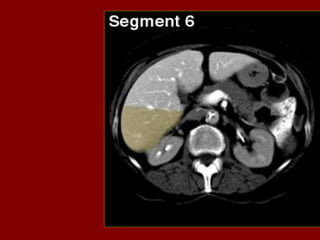

G H PB Corpo do pâncreas R Costela RP Pelve renal PC Confluência portal RA Músculo reto do abdome RPV Veia porta PF Gordura perirrenal RC Pilar direito do diafragma RRA Artéria renal direita PH Cabeça do pâncreas RF Gordura retroperitoneal RRV Veia renal direita PS Músculo psoas RG Glândula supra-renal dir. RU Ureter direito PT Cauda do pâncreas RHV Veia hepática direita S Processo espinhoso PU Processo uncinado do pâncreas RIL Lobo inf. do pulmão dir. SA Artéria esplênica PV(R) Ramo direito da veia porta RK Rim direito SC Medula espinal QL Músculo quadrado do lombo RL Lobo direito do fígado SF Flexura esq. do colo SI Intestino delgado SV Veia esplênica SMA Artéria mesentérica sup. Tc Coto transverso SMV Veia mesentérica sup. TVP Processo transverso Sp Baço Xp Processo xifóide St Estômago